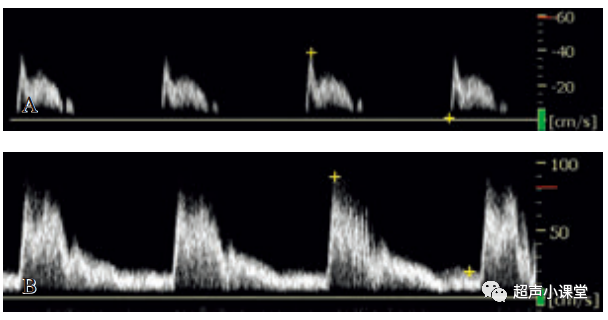

(四)狭窄远心段的搏动性改变

严重动脉阻塞远段多普勒波形出现衰减的波峰.

此波形表现收缩加速时间延长,收缩峰变圆钝,收缩峰值低于正常,舒张期血流增加.

也可用“小慢波”来形容.它可以明确提示检测部位的近端存在管腔阻塞.